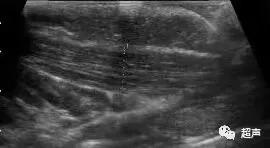

正常胸锁乳突肌彩超表现是这样的